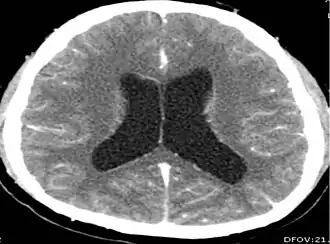

CT scans and magnetic resonance imaging (MRI) give objective information about the number and pattern of lesions, the stage of healing, and how the immune system is responding to the parasites.[19] MRIs are better for evaluating different spatial planes and provides clearer images, which helps in identifying small lesions at the back of the brain or near the skull that may be missed on CT scans. CT scans are more sensitive at detecting calcium buildup in the brain due to its ability detect calcifications in the brain.[30]

Live vesicular cysts are small, round lesions with little swelling around them and do not need contrast for imaging. The tapeworm head (scolex) usually appears as an asymmetric nodule inside the cysts. Multiple live cysts with these heads corroborate the diagnosis. Once the cysts begin to break down (colloid cysts), their borders become unclear, they are surrounded by swelling and exhibit significant ring or nodular contrast enhancement. Calcified cysticerci are shown on CT scans as non-enhancing hyperdense nodules without swelling.[20]